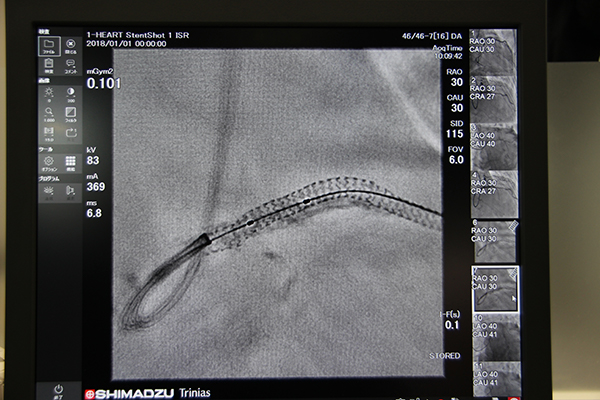

血管撮影システム「Triniasシリーズ」は,「Trinias C16 unity edition」の実機を展示し,新オプションであるチルト機能が搭載された新しいカテーテルテーブルや,ノイズを低減して治療デバイスを鮮明に表示する“SCORE StentShot”,造影画像から自動で長尺画像を作成する“SCORE Chase”などの高機能アプリケーションをアピールした。

新開発のチルトテーブルと組み合わせた「Trinias C16 unity edition」

デバイスを明瞭に描出する“SCORE StentShot”